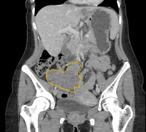

Multiple intestinal intussusceptions caused by highly impaired gastrointestinal motility in a patient with chronic cannabis consumption

Olga Prokopchuk and others

Journal of Surgical Case Reports, Volume 2019, Issue 5, May 2019, rjz160, https://doi.org/10.1093/jscr/rjz160